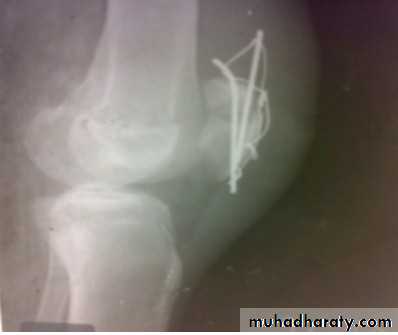

Supracondylar fracture with its fixation by L – plate and screws

dynamic condylar screw and plate

In old internal fixation is often preferable and the patient can get out of bed sooner (dynamic condylar screw and plate) .